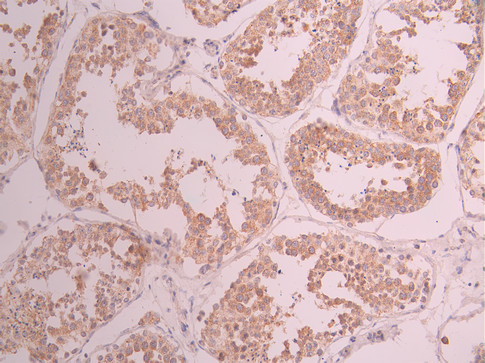

IHC image of CSB-RA105098A0HU diluted at 1:100 and staining in paraffin-embedded human testis tissue performed on a Leica BondTM system. After dewaxing and hydration, antigen retrieval was mediated by high pressure in a citrate buffer (pH 6.0). Section was blocked with 10% normal goat serum 30min at RT. Then primary antibody (1% BSA) was incubated at 4°C overnight. The primary is detected by a Goat anti-rabbit polymer IgG labeled by HRP and visualized using 0.05% DAB.